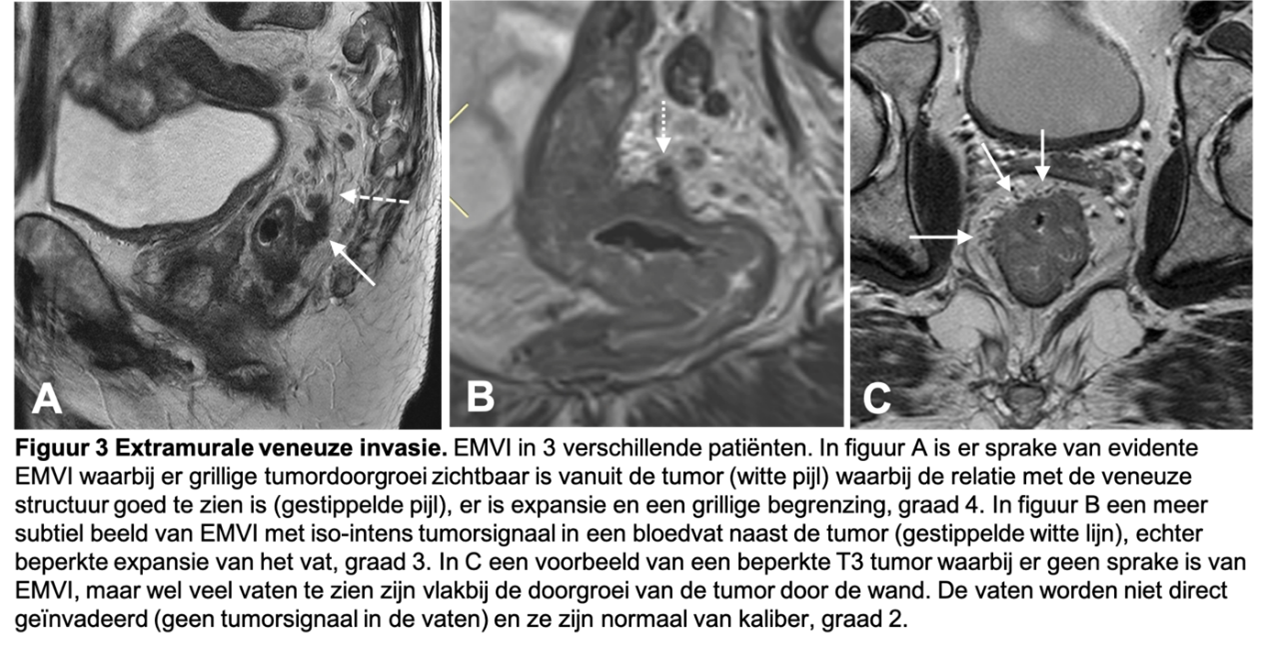

EMVI is van belang omdat het een belangrijke voorspeller is van slechtere ziektevrije overleving, met name de kans op afstandsmetastasen is hoger bij patiënten met EMVI (Chen, 2021). EMVI is gedefinieerd als directe tumordoorgroei (met intermediair signaal) in een nabijgelegen vat, waarbij opvulling van het bloedvat met tumor, al dan niet gepaard met expansie van het vat en/of irregulaire begrenzing van het vat. Er zijn 5 categorieën in de EMVI-gradering: (0) geen nodulaire doorgroei door de rectumwand en afwezigheid van bloedvaten nabij de tumor, (1) minimale extramurale stranding van de tumor, maar geen vaten nabij, (2) stranding nabij vaten, maar geen tumorsignaal in het lumen (3), intermediair tumorsignaal continu met de primaire tumor in een bloedvat en (4) intermediair tumorsignaal met (nodulaire) expansie van het geïnvadeerde bloedvat. Alleen graad 3 en 4 EMVI dienen als EMVI+ te worden beoordeeld. Het is van belang om alleen de aanwezigheid van een bloedvat naast de tumor niet als EMVI te overstadieren (zie figuur 3 voor voorbeelden van graad 2, 3 en 4 EMVI).

Figuur 3. Extramurale veneuze invasie